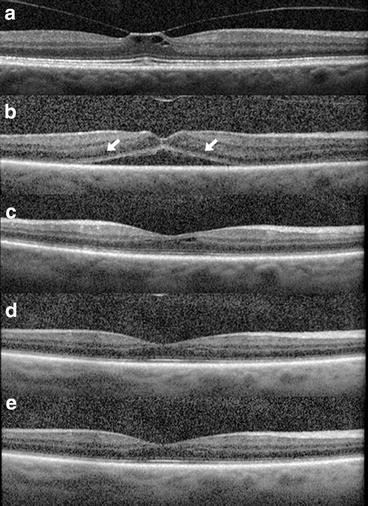

Several post-marketing reports have described the nature of OCT changes following ocriplasmin use, including ellipsoid layer disruption and accumulation of subretinal fluid (SRF, Fig. 2) [14, 2730]. Notably, ellipsoid zone alterations were not reported in the MIVI-TRUST trial data, likely owing to the use of time-domain OCT rather than spectral-domain OCT (SD-OCT).

Optical coherence tomography alterations post ocriplasmin use. A 62-year-old male with VMT of the right eye (a). Following intravitreal injection of ocriplasmin, VMT was released (b) at day 7. Ellipsoid layer attenuation and accumulation of subretinal fluid was present (arrows) and vision decreased from 20/50 at baseline to 20/80. Ellipsoid layer changes and subretinal fluid progressively resolved as shown at day 30 (c), day 60 (d), and day 90 (e). Visual acuity was 20/25 on day 60 and was maintained through the follow-up period thereafter